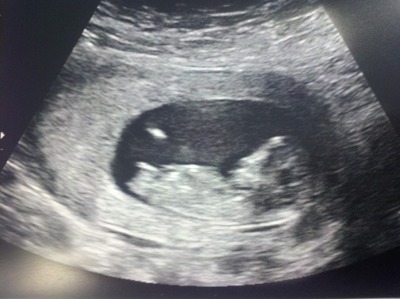

I think girl... Esp from middle pic

That second pic, is so very girly!!!!

The second pic looks super girly to me!